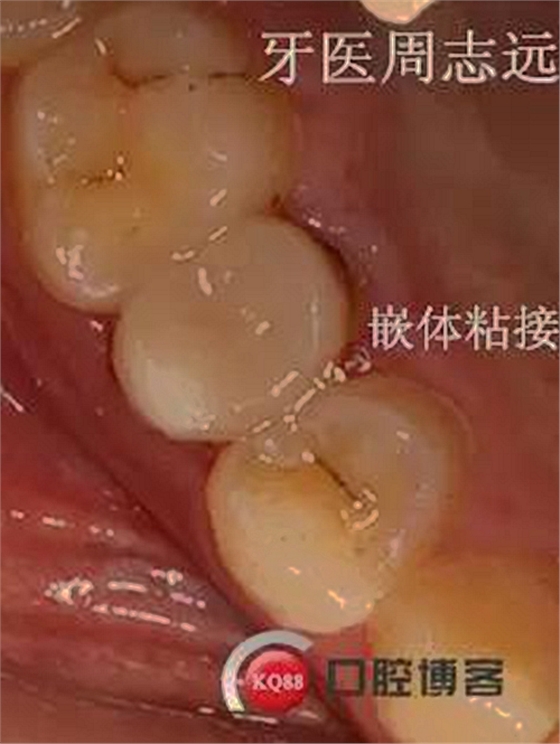

患兒于15年右上恒5牙髓炎就診,檢查發(fā)現(xiàn)根尖孔未閉合,與家長溝通后采取根尖誘導(dǎo)成形術(shù)。RCT完成后vitapex暫封根管,要求半年復(fù)查一次。16年復(fù)查根尖未見明顯異常,但根尖孔未完全閉合,沒有完全鈣化,vitapex再暫封根管繼續(xù)誘導(dǎo)。17年復(fù)查發(fā)現(xiàn),根尖孔完全閉合,X線片顯示形成鈣化屏障,完成根充。由于牙體缺失過多,并且患者后期可能需要進(jìn)行正畸治療,考慮到患者家庭條件因素,選擇進(jìn)行樹脂嵌體修復(fù)。后期等患者建合完成或者達(dá)到矯正時(shí)機(jī)時(shí)再根據(jù)情況選擇修復(fù)方式。告知定期復(fù)查。

總結(jié):患者屬于比較配合醫(yī)囑類型,但是由于家境一般,孩子又希望臨時(shí)修復(fù)體能比較美觀一點(diǎn),只能綜合考慮治療方案,待咬合建立完成后進(jìn)行瓷嵌體修復(fù)或者樁冠修復(fù)。